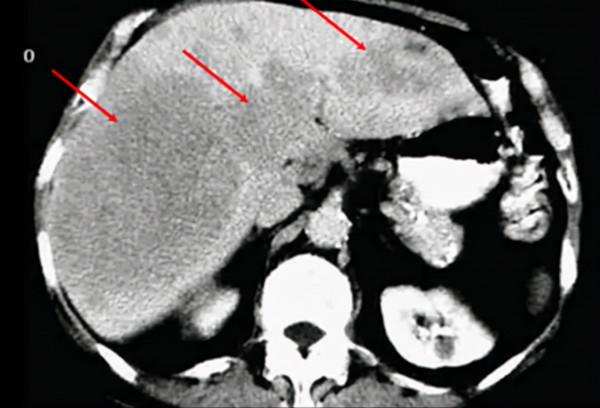

酒精性脂肪肝

60歲女性前來接受新的患者評估,自述一年前失去丈夫後一直患有抑鬱症,每天喝大約60g酒。最近在急診室就診期間接受了腹部CT掃描(如圖3)。

在回顧CT 掃描時,考慮哪些變化是繼發於酒精,包括酒精性肝脂肪變性、酒精性肝炎、酒精性肝硬化、肝細胞癌。答案是酒精性肝脂肪變性。每天攝入超過60g酒精會導致肝臟的形態變化,出現肝臟的脂肪替代或肝脂肪變性。酒精性脂肪肝被認為是由於脂肪酸和甘油3-磷酸鹽的增加.較新的成像技術,如雙能CT,顯示出量化脂肪變性程度的潛力。肝脂肪變性是可逆的,但如果攝入酒精沒有減少,就會發生酒精性肝炎,隨後是酒精性肝硬化。